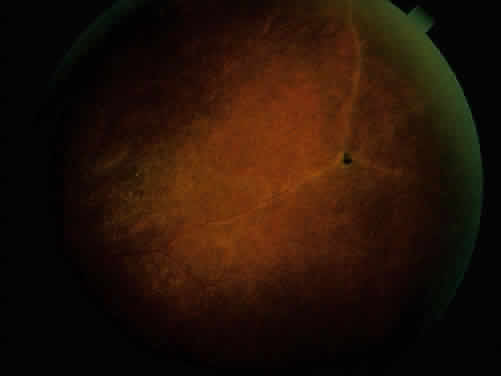

The associated arthritis and iridocyclitis, however, are similar in both conditions. Peripheral arthritis is seen in approximately 12% of patients with ulcerative colitis and approximately 20% of patients with regional enteritis. Radiographic evidence of sacroiliitis has been reported to show an incidence of approximately 18% and to be equal in both sexes in both conditions. Clinical spondylitis is seen in association with bowel inflammation in 4% to 7% of these conditions. The overall incidence of HLA-B27 in these two conditions may be slightly elevated, but is similar to that in the normal population. HLA-B27 is present in 53% to 75% of patients who have both spondylitis and inflammatory bowel disease. The sacroiliac involvement is frequently asymmetric (Fig. 5). It is not clear whether the spondylitis is secondary to the inflammatory bowel disease or to an overlap of the conditions. Spondylitis occurs before the bowel disease in 25% of patients, and there seems to be little correlation in the activity of symptoms between the sacroiliitis and the bowel disease. Colectomy does not affect the sacroiliitis, even when the bowel disease is improved. This is in contrast to the activity of the peripheral arthritis, which does seem to parallel the activity of the inflammatory bowel disease in 60% to 74% of patients. The peripheral arthritis also precedes the bowel disease in 7% to 11% of patients.33,36,37 It is not clear how these relate to the associated iridocyclitis.

Fig. 5. Asymmetric sacroiliitis with sclerosis and narrowing of right sacroiliac joint in a 22-year-old woman with inflammatory bowel disease and iridocyclitis.

Ocular inflammatory changes include conjunctivitis, episcleritis, keratitis, acute and chronic iridocyclitis, and posterior changes as well.38–43 The acute iridocyclitis is milder and frequently not accompanied by as much pain, photophobia, and redness as in the acute iridocyclitis associated with other spondyloarthropathies. Mild injection of the conjunctival and episcleral vessels and blurred vision may be the only symptoms of an acute flare of activity. The endothelium of the cornea usually has cellular debris and poorly formed keratic precipitates in the lower cornea. The anterior chamber contains cells and moderate flare, and a protein clot is not infrequent in the pupil, with early formation of posterior synechiae (Fig. 6); however, the synechiae are usually more easily broken than in ankylosing spondylitis and Reiter's syndrome.44 Treatment with topical corticosteroids and mydriatics is usually effective. The activity of the iridocyclitis has been reported to follow the activity course of the inflammatory bowel disease. Systemic treatment of inflammatory bowel disease has been noted to help the ocular inflammation. Decreasing the systemic treatment occasionally allows ocular inflammation to become visible and requires close observation and appropriate increase in local therapy.39,44–46 Surgical resection of inflamed bowel for other medical reasons has sometimes been reported to coincide with lessening of ocular inflammation,44,46 but these observations need better evaluation.42 Posterior segment manifestations, including retinal and choroidal vascular disease, are also sometimes noted.47,48

Fig. 6. Partial posterior synechiae and fibrin clot in pupil with iridocyclitis and Crohn's disease.